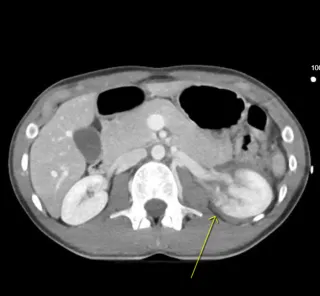

Renal trauma represents approximately 10% of all abdominal injuries and is most often secondary to blunt mechanisms such as motor vehicle collisions, falls, or sports injuries. ...more

Imaging ,CT Scan

November 05, 2025•3 min read